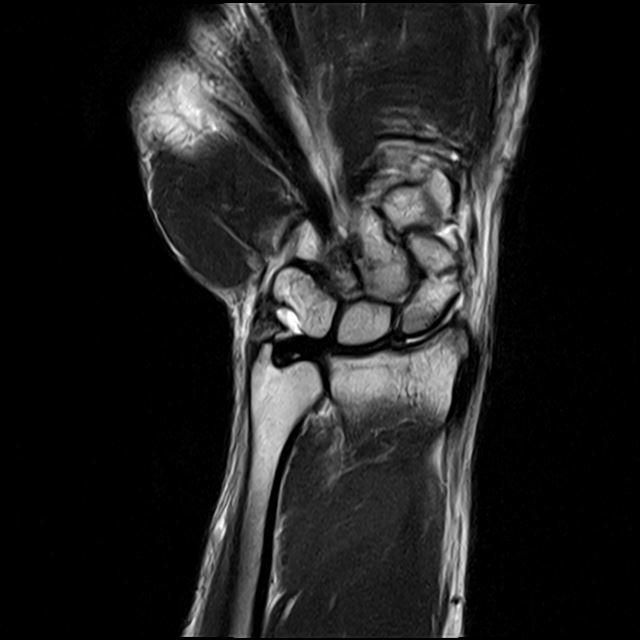

주상골 골절입니다. 제 상태가 정확히 어느정도일까요

사진은 mri 사진이고 엑스레이와 씨티는 잘 안보이긴합니다.

MRI상 “미세 골절.인대손상“은 보이지만, X-ray.CT에서 전위가 뚜렷하지 않다면 “경계선 상황”으로 보입니다.

수술 적응증은 보통 “뼈 전위, 관절면 불위치, 불안정성“이 명확할 때입니다.

지금처럼 의견이 갈리면 “손목 전문 정형외과에서 CT 재판독“이나 추적촬영이 도움 됩니다.

통증.기능 저하가 크지 않다면 “단기 깁스 후 재평가“ 합리적인선택일 수 있습니다.